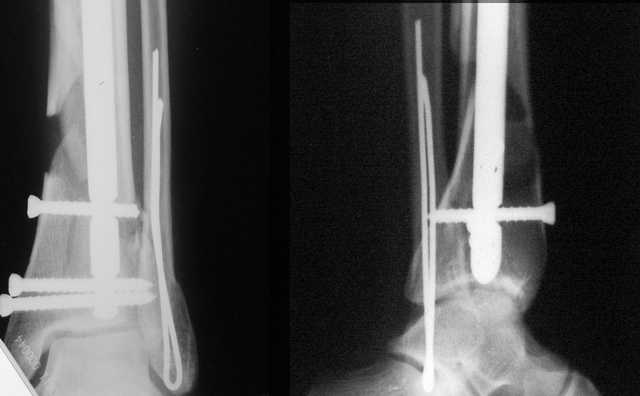

Да и нет! Зависит от перелома и способа остеосинтеза. А результат? (01)

А.Миронов

Мы же говорили о проксимальном плече. При переломе tibia, конечно, речи о двух Y-спицах нет. Еще раз о них - пружинящая подвижность без "срезающих" перемещений фрагментов - дополнительный стимул к образованию периостальной мозоли.

А в данном случае - у нас был бы применен locked nail с еще меньшими дырочками на коже и с возможностью полной нагрузки немедленно после операции. Какие тут аргументы в пользу выбора пластины, а не интрамедуллярного гвоздя?